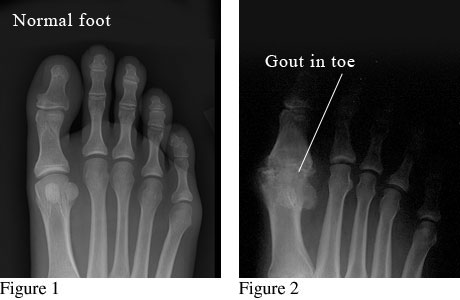

X-ray images of a normal foot and a foot with gout in the big toe

Image courtesy of Paul Traughber, M.D., Boise, Idaho.

Figure 1 is an X-ray of a normal foot with healthy bones and joints.

Figure 2 is an X-ray of a deformed toe joint caused by long-term gout.